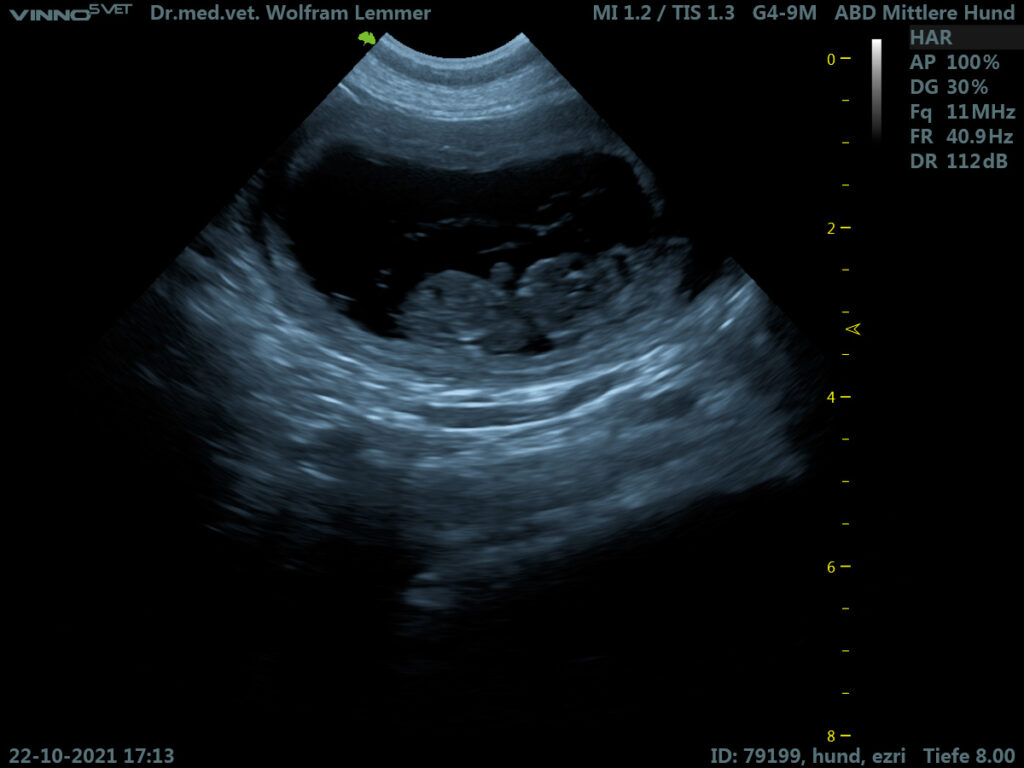

Die Ultraschalluntersuchung am 22. Oktober zeigte mehrere gutentwickelte Föten, die in ihren Fruchtblasen hüpften. Die kleinen Herzchen schlagen zu sehen, ist immer wieder ein ergreifender Moment.